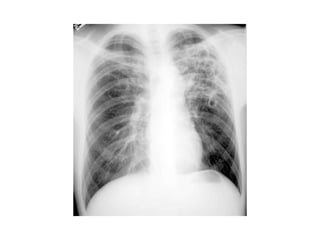

• Rx

– A TODOS LOS PACIENTES CON SOSPECHA DE Tb

– Hallazgos radiográficos

• Anormal

– Cavitaria o no cavitaria

– Estabilizada, progresión o mejoría